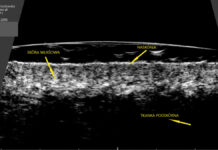

Diagnostyka kosmetologiczna na serio Część 4. Ultrasonografia

W ostatnich latach do gabinetów kosmetologów wkroczyła najnowocześniejsza i jednocześnie najbardziej zaawansowana metoda diagnostyczna skóry-ultrasonografia. Obrazowanie ultrasonograficzne pozwala zobaczyć skórę od środka. Ma zatem...